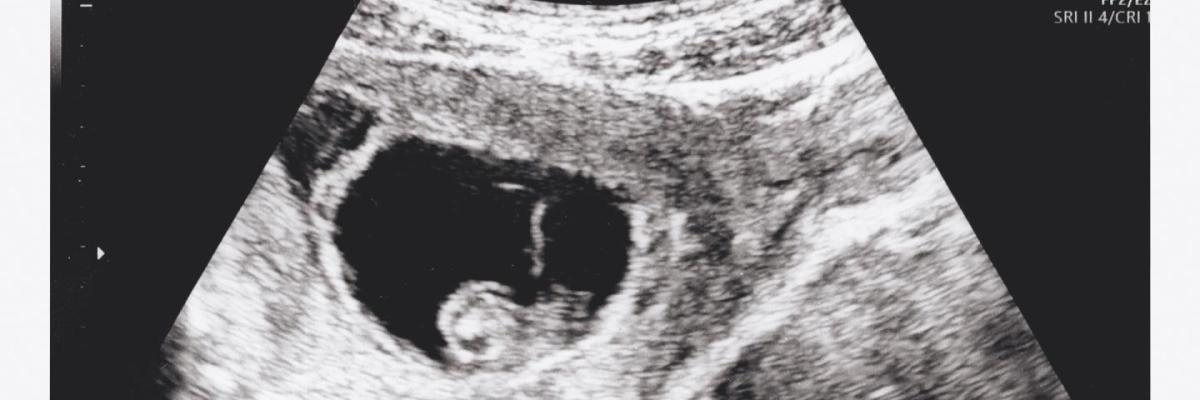

From August 15, pregnant women in Hungary who want an abortion must first listen to the heartbeat of their foetus before going through with the procedure, according to an announcement from Minister of the Interior Sándor Pintér, who is also responsible for healthcare and education in Hungary.

‘The presented medical findings must record that the healthcare provider presented the factor indicating the vital functions of the foetus to the pregnant woman in a clearly identifiable manner,’ said the minister. He said that the new ministerial decree requiring pregnant women to listen to the baby’s heartbeat was not a new law but simply a continuation of the 1992 abortion law, which has not been changed since it was passed.

In Hungary, abortion is allowed until the 12th week of pregnancy under certain conditions, including the pregnancy endangering the life of the mother, if the foetus has a high risk of being born malformed, the pregnancy resulting from rape, and if the woman is in a severe crisis. Certain allowances also push the abortion limit to the 18th week of the pregnancy. SOURCE ON REQUEST.